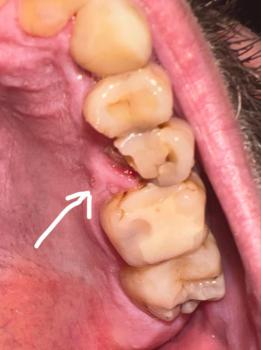

What Is Seen in This Case

The image shows a localized swollen and red gum area near a lower back tooth, with signs of infection along the gumline. The tongue is positioned close to the affected area and appears irritated, likely due to contact with the inflamed tissue or drainage from the infection.

The tooth structure looks intact, but the surrounding gum tissue is clearly unhealthy.

This case shows a localized gum abscess near a lower molar, with early involvement of nearby soft tissues. Early drainage and cleaning usually result in good healing outcomes.